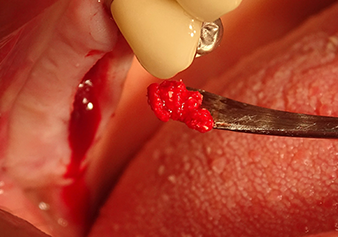

Following an intermediate check (Fig. 4) a further preparation step was performed (Fig. 5). Afterwards, the hydraulic Z35P instrument was used to lift the membrane to the desired position (Fig. 6 and 7). This was followed by further piezosurgical preparation of the implant bed, concluded with a rotary bur and shoulder milling cutter up to the implant diameter of 4.8 mm. Before the implant was inserted, the augmentation material (particle size approx. 0.8-1.6 mm) was introduced underneath the Schneiderian membrane (Fig. 8).